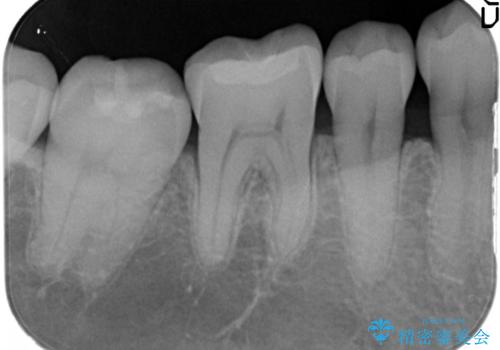

治療したむし歯の再治療。セラミックにしたい!

- 以前治療した歯が欠けたことを主訴に来院されました。

見た目もよく強度の高いものでの修復を希望されましたのでセラミックインレーにて修復しました。

当院でのセラミックインレーは歯とのつなぎ目を拡大鏡で確認して精度高く仕上げるため、むし歯のリスクを限りなく少なくできるよう治療します。